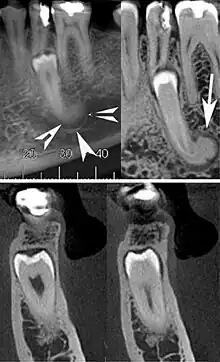

Cone beam CT images showing a well-defined hyperdense round lesion attached to the root of supernumerary mandibular tooth (arrow head) with a surrounding hypodense rim.[1]

A cementoblastoma in a radiograph appears as a well-defined, markedly radiopaque mass, with a radiolucent peripheral line, which overlies and obliterates the tooth root. It is described as having a rounded or sunburst appearance. There is usually apparent external resorption of the root where the tumor and the root join. Severe hypercementosis and chronic focal sclerosing osteomyelitis are lesions to consider in the differential diagnosis of this lesion.